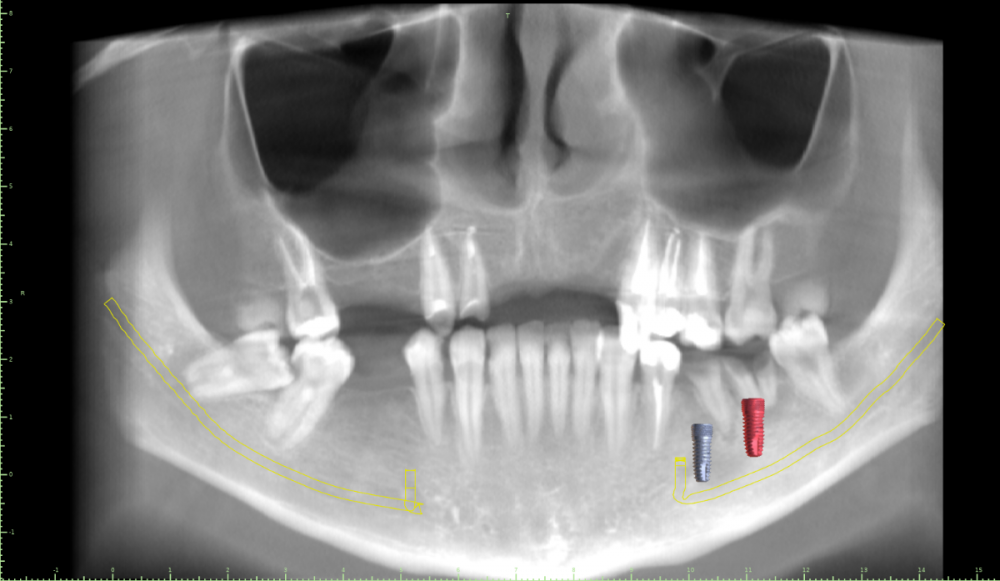

Женька Опубликовано 19 июля, 2021 Автор Поделиться Опубликовано 19 июля, 2021 @Евгений Ходыкин Глубже этого "перешейка" тонкого? планирую вот так Ссылка на комментарий

Irouil Опубликовано 26 июля, 2021 Поделиться Опубликовано 26 июля, 2021 Я бы придал имплантам немного ангуляции Ссылка на комментарий

Евгений Ходыкин Опубликовано 27 июля, 2021 Поделиться Опубликовано 27 июля, 2021 (изменено) 20.07.2021 в 00:03, Женька сказал: планирую вот так У Вас 3 варианта: 1. Как спланировано на скрине Вашем + можно конденсорами поработать. 2. Топить глубже. 3. НКР 4. Решать, конечно же, Вам)) Изменено 27 июля, 2021 пользователем Евгений Ходыкин 1 Ссылка на комментарий